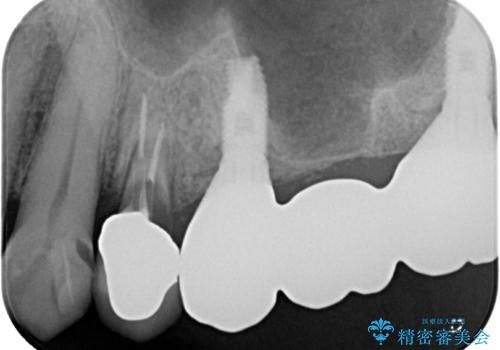

- 土台の歯が割れてしまって、歯がグラグラしているとのことで来院された患者様です。

いずれの歯も抜歯が必要な状態であり、抜歯即時埋入によるインプラント治療を行うこととしました。

右上奥歯は骨欠損の範囲が広いため、抜歯即時埋入は可能であっても、即日で仮歯を装着する即時荷重は難しいと判断されたため、手前の歯まで仮歯を装着することとしました。